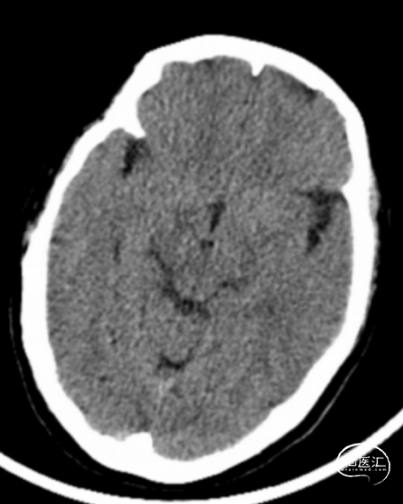

术前头颅CT示:颅内未见明显异常。

术后24小时头颅CT:右侧基底节区少量出血及低密度灶。